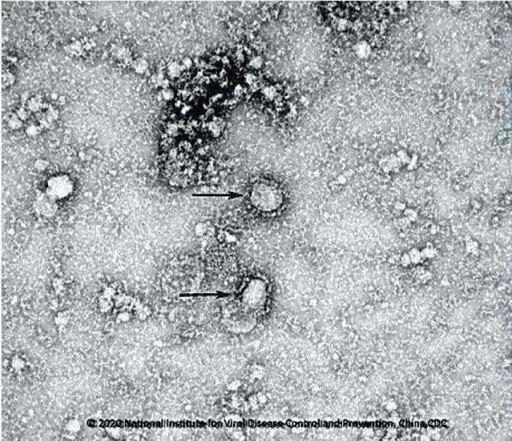

تعداد زیادی نمونه از بیماران مبتلا به این ویروس در آزمایشگاههای چین و سازمان جهانی بهداشت بررسی شده و متخصصان این ویروس را از خانواده “ویروس کرونا” شناختهاند.

تاکنون ۶ نمونه از ویروس کرونا کشف شده بود و با مورد اخیر تعداد آن به هفت میرسد.

تحقیقات نشان میدهد که کدهای ژنتیکی این ویروس نزدیکی زیادی به ویروس سارس دارد.